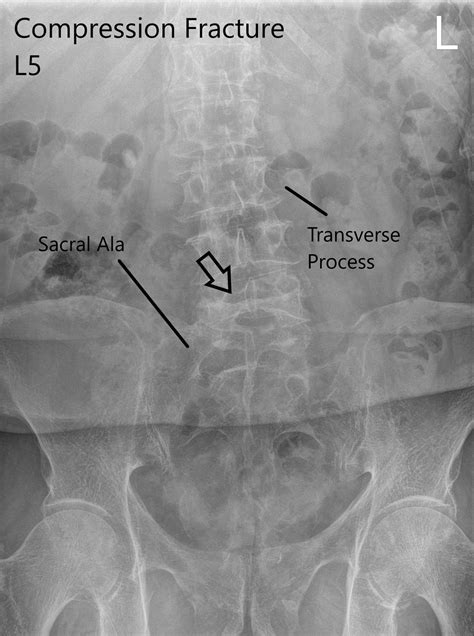

Alright, so here’s the juicy part: what’s the actual code for an L1 compression fracture ? The specific code can vary a little depending on the exact details, like whether it’s a new injury or a result of something else. However, the most common codes you’ll encounter are related to spinal compression fractures. The code helps pinpoint the location of the fracture. Depending on the nature of the fracture and any other conditions, the code may vary, but they all fall under a particular category. For a general compression fracture of the lumbar spine (L1 being part of the lumbar region) , you’re likely looking at codes within the M48 category, which relates to other spondylopathies. For example, a common code used might be M48.08 , but always double-check with your doctor or healthcare provider for the most accurate and up-to-date code for your specific situation. This code is the official designation that doctors use when they document your diagnosis. The code helps medical professionals communicate effectively about a patient’s condition. The code also helps in tracking the prevalence of spinal fractures. Understanding the ICD-10 code for your L1 compression fracture is essential for you. It enables effective communication with healthcare providers. The code is necessary for insurance claims and also helps ensure the right treatments. Healthcare providers use the codes to submit claims to insurance companies for reimbursement. Knowing the code can help you understand what procedures are being billed and why. The code is important for researchers to analyze health data. This information helps improve patient care and develop better treatment options. The code is important for tracking the prevalence of spinal fractures. This helps in public health planning and healthcare resource allocation.